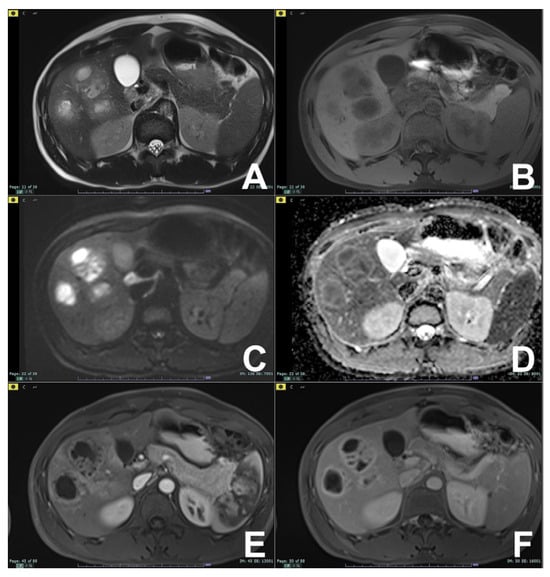

| Follow-up oncological Patient | HASTE T2 | AXIAL | -- | -- | Anatomy and liquids analysis |

| INDICATIONS: MRI is the technique of choice in young patients and pregnant women after a unclear US finding. Moreover, it is useful even after a CT with undefined diagnosis for all patients. It can be alternated to CT in young patients with a long follow-up. | HASTE T2 | CORONAL | -- | -- | Anatomy and liquids analysis |

| DWI b 0–50–400–800 | AXIAL | -- | -- | DWI b50 increases the sensitivity of mets detection | |

| GRE T1 IN/OUT | AXIAL | -- | -- | Steatosis | |

| GRE T1 3D DYNAMIC | AXIAL | PRE-ART 25″-PORTAL 70″-LATE 180″ | YES | HBP increases the sensitivity of metastases detection | |